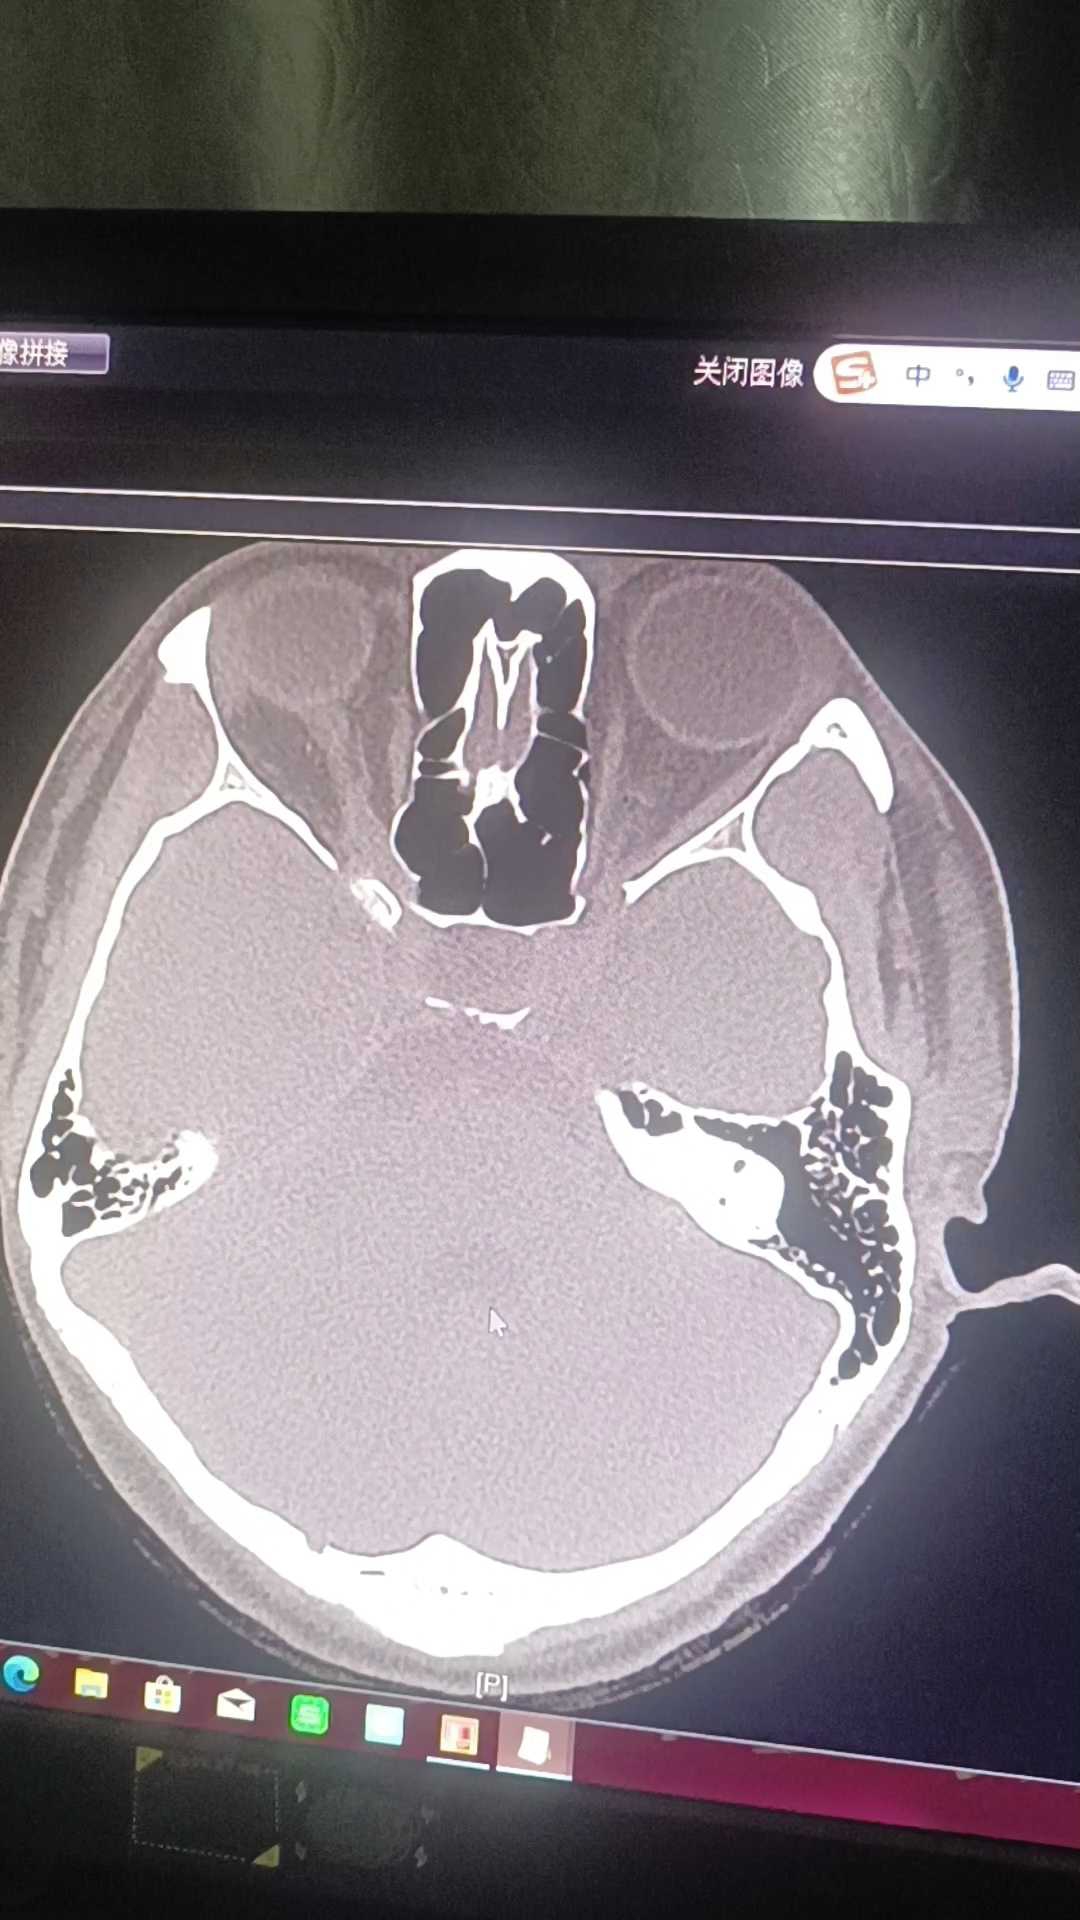

患者,37岁,女性,头部外伤后头痛,头晕,恶心2天入院。自诉右耳听力下降,伴耳鸣,行相关检查如下